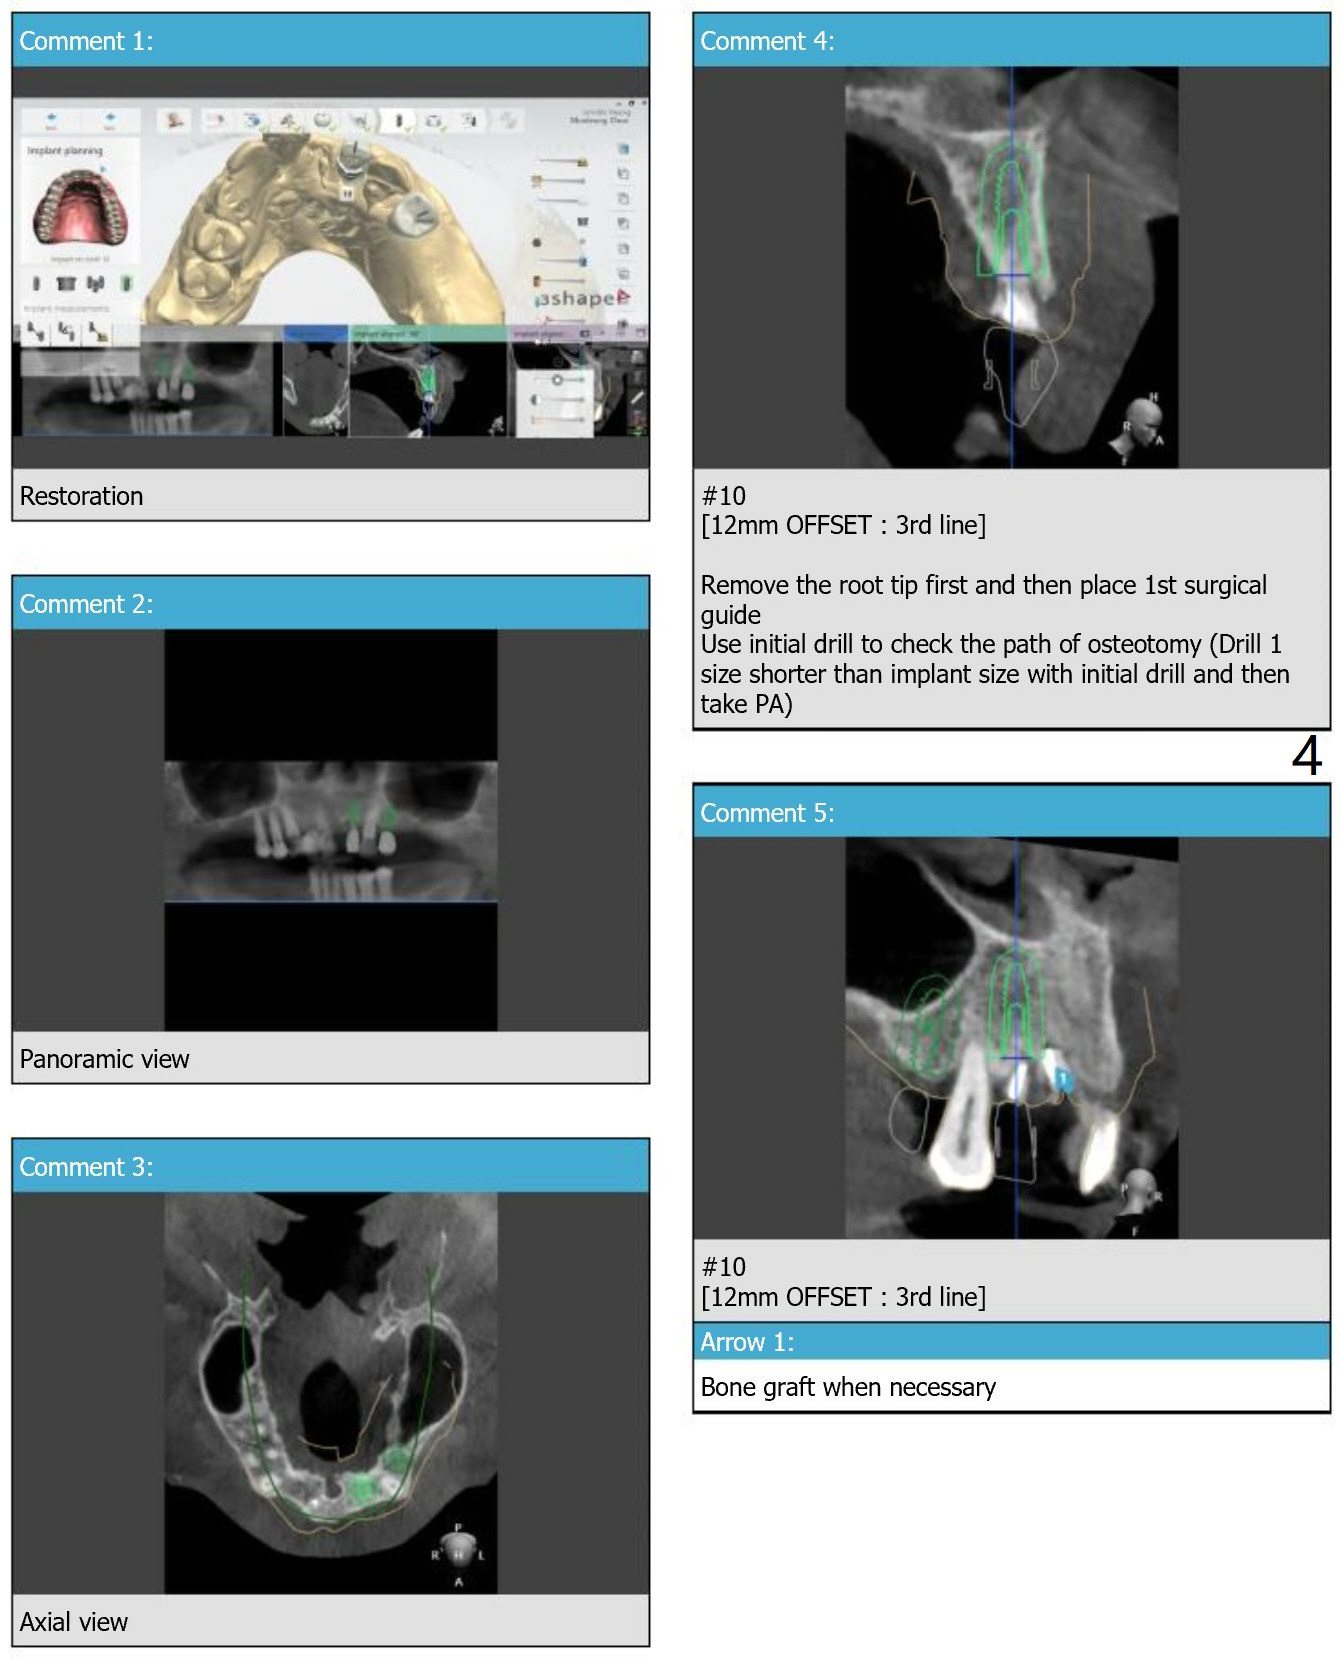

We have re-conducted the implant planning of this patient for #10 & 12.  This case requires both narrow navi guide kit and regular navi guide kit. And for #10, 2 surgical guides with different offsets will be sent.

The site of #10 is chosen over #9 for an implant and cantilever FPD because of the bone width and further away from the Incisive Foramen.